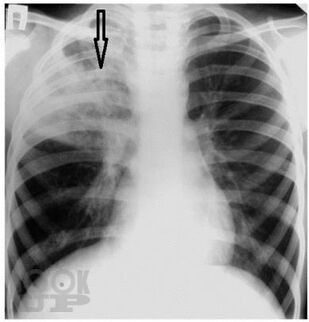

Пневмония у детей

Излагается современная информация по классификации пневмонии у детей, ее эпидемиологии, этиологии, клинических особенностях в зависимости от этиологических и анатомо-физиологических факторов и фоновых заболеваний. Значительная часть пособия посвящена диагностике, принципам современной антибактериальной терапии с последних достижений в педиатрии.